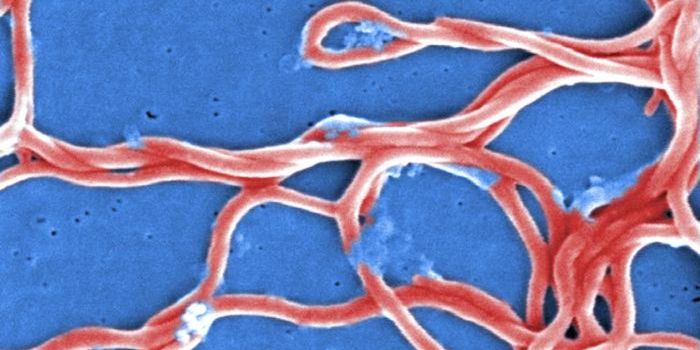

APR 29, 2016Clinical & Molecular DXEbola infection and transmission caused a huge international health crisis in 2015 in West Africa, the site of the large ...

FEB 11, 2022MicrobiologyEbola virus has caused several major outbreaks in recent decades. Its high death rate and disturbing symptoms have made ...